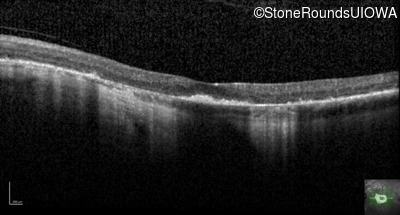

Optical Coherence Tomography - Right - 20/20 -2

Exemplar / OCT Stack